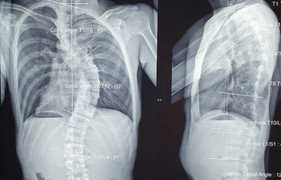

Cột sống cong vẹo hình con rắn khiến bé gái 13 tuổi đi lại, sinh hoạt khó khăn được các bác sỹ BV Bạch Mai (Hà Nội) nắn chỉnh thành công trong ca mổ xuyên đêm.

Một thiếu nữ 15 tuổi vừa cải thiện chiều cao thêm 7cm sau khi ca phẫu thuật nắn chỉnh cột sống bị vẹo đến hơn 100° thành công tốt đẹp.

Bệnh nhân nữ 15 tuổi mắc hội chứng Marfan dẫn tới ngón tay, chân dài hơn người bình thường, cột sống bị vẹo 69°, cong như hình chữ S.